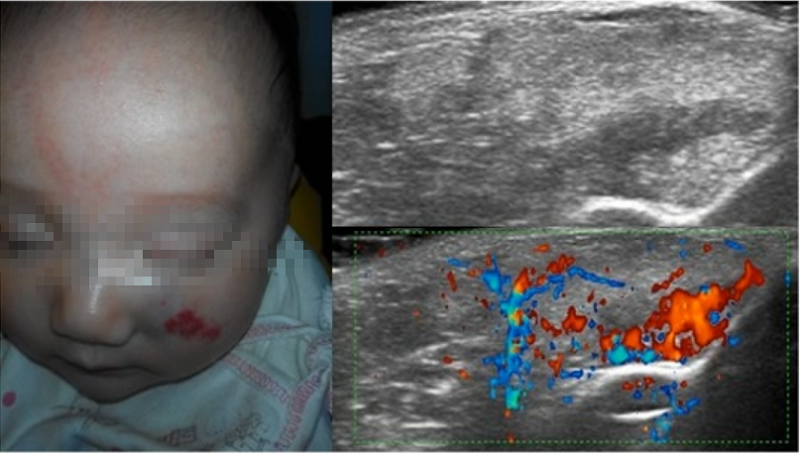

大多数血管瘤可以诊断,无需额外检查。但如果血管瘤位置深,则难以通过肉眼与其他血管畸形或肿瘤相区别,需借助影响学检查(如图5、图6)。如果仍不能确诊,还需要行皮肤活检。

▲ 图5 彩超检查